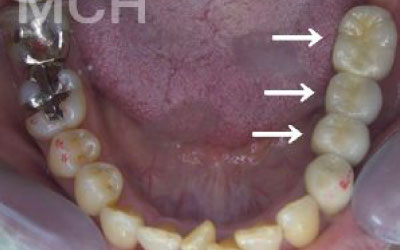

お口の状態や噛み合わせによるので一概には言えないですが、基本的には奥歯がお勧めです。

特に大臼歯と言われる一番奥と奥から二番目の歯の部分です。

噛み合わせの力の60%以上がこの奥から2つの歯で支えているので、ここをしっかりインプラントで治療するのはお勧めです。